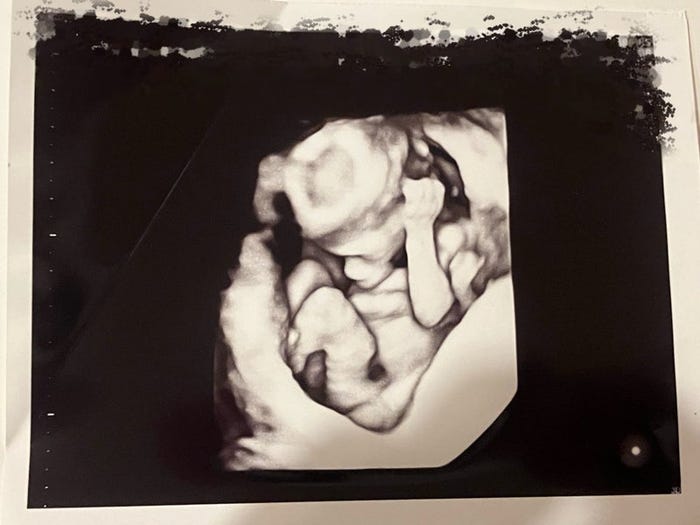

さらに「お医者さん、看護師さん、家族や友達、いつも応援して下さる皆さんのエールのおかげで、新しい命を授かることができたと思っています!ありがとうございます」と感謝もつづったネイボール。「これから生まれてくる赤ちゃんのためにも、長生きしたいと思います!」とし、「妻はまだつわりが続いていて、大変そうだけど不妊治療の記事も、少しずつあげていきたいと思っています」とエコー写真を手にした自身と妻の2ショットを公開して締めくくった。